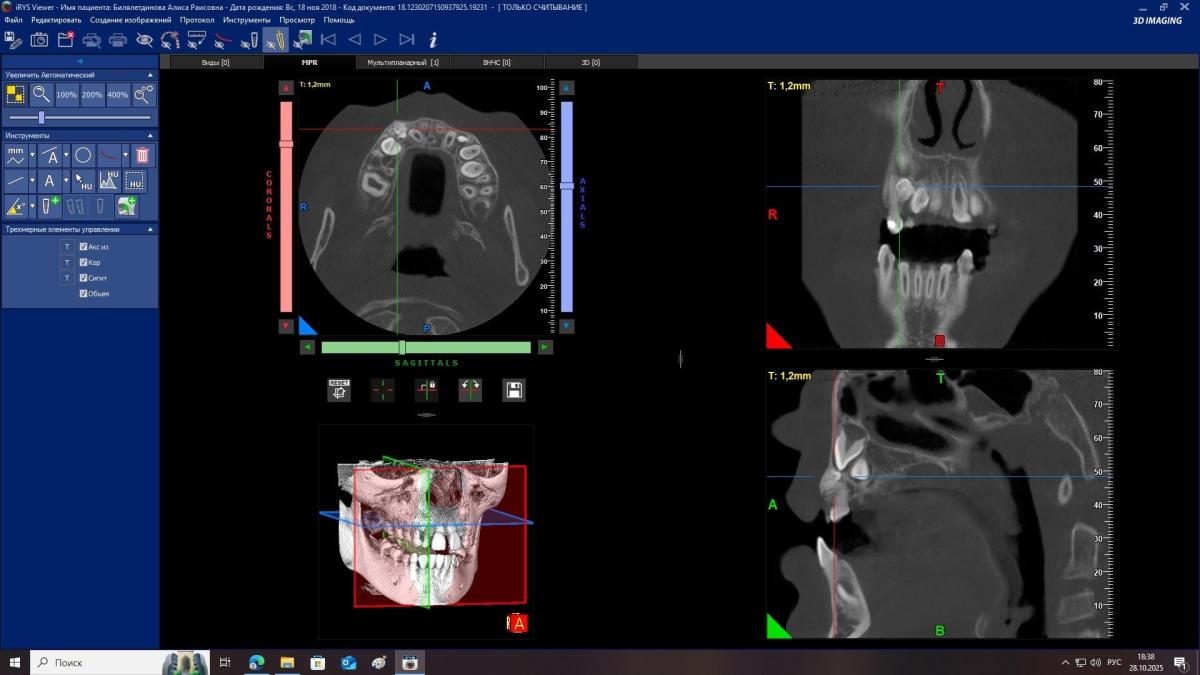

Здравствуйте, Ребекку 7 лет. Отсутствуют нижние зачатки 5 зубов. Верхний зачаток пятерки в недоразвитом состоянии и перевернут . Что с ним будет? Возможно ли что вырастет как надо? И основной вопрос- верхний клык (снимок прилагаю) между молочным и коренным обнаружено какое-то образование- это лишний зуб? Как его удалять? Вырывать молочный клык сейчас , далее удалять лишний и уже после ждать прорезывания постоянного? Или ждать пока молочный сам выпадет?

SGanem, мы были у двух ортодонтов. Один говорит ждать до 8 лет, другой - что ждать не надо надо идти под наркоз сейчас и удалять молочный и лишний клыки

Kseniya2, удалять обязательно и чем скорее, тем лучше!